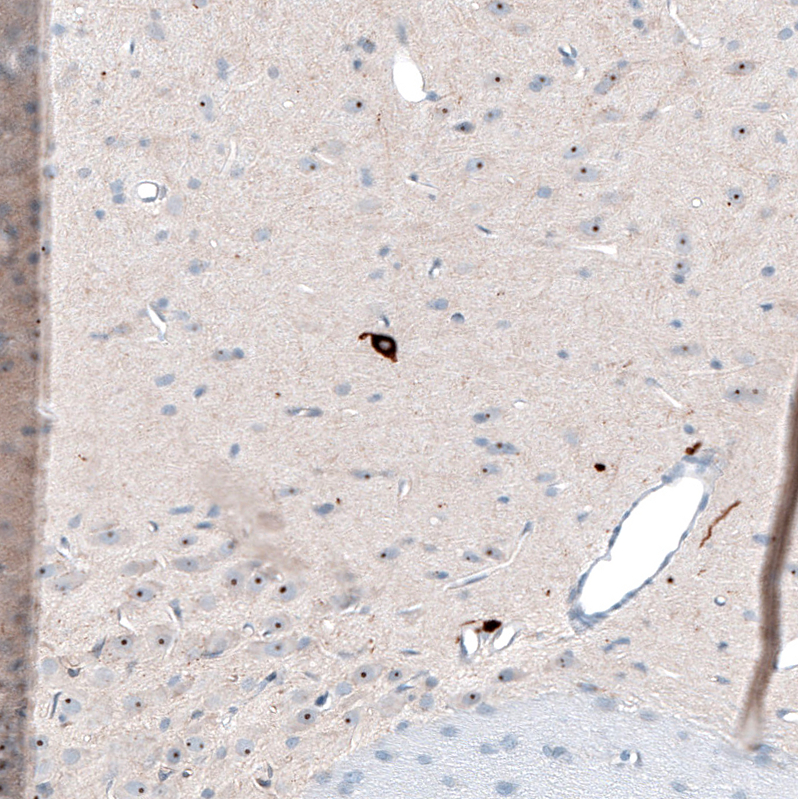

Immunohistochemical staining of human hypothalamus shows moderate cytoplasmic positivity in a subset of neurons.